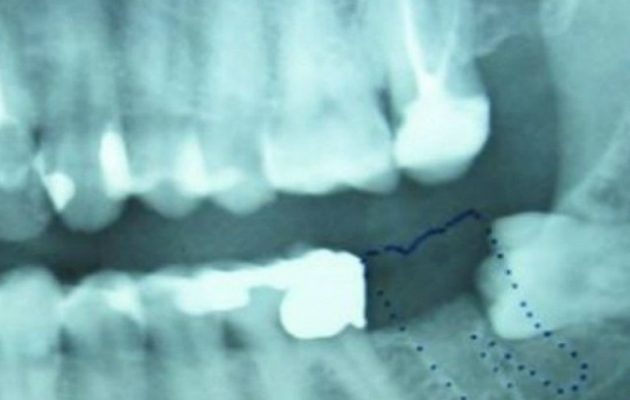

Ο μικρός λοιπόν, ενώ είχε αλλάξει σχεδόν όλα του τα δόντια, ένα δεν είχε βγει ακόμα, με αποτέλεσμα η θέση του αριστερού φρονιμίτη στην άνω γνάθο να είναι κενή.

Εκεί όμως τους περίμενε μία έκπληξη, καθώς αυτό που είχαν δει ήταν το χαμένο δόντι.

«Συνήθως αυτό αντικαθίσταται με ένα μόνιμο στην ηλικία των 12 ετών», ανέφερε μεταξύ άλλων η ανακοίνωση του νοσοκομείου, τονίζοντας πως η συγκεκριμένη περίπτωση είναι πολύ σπάνια.

Ο γιατρός που ανέλαβε την επέμβαση, Ντμίτρι Ταρούσιν, τόνισε πως υπάρχουν περιπτώσεις που δόντια έχουν μεγαλώσει στον πνεύμονα, αλλά μέσα σε γεννητικά όργανα, δεν έχει καταγραφεί άλλη φορά.